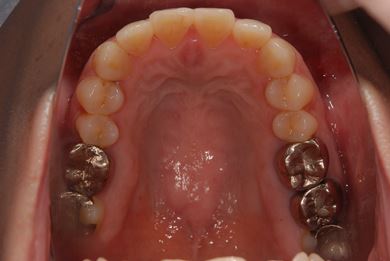

| 性別/年齢 | 女性 / 39歳 | ||||||||||||||||||||||||||||||||

| 主訴 | 右奥歯の虫歯と、右奥のインプラント治療について相談。 | ||||||||||||||||||||||||||||||||

| 治療方針 | 右下奥欠損部分をインプラント治療にて、機能的・審美的回復を行う。 | ||||||||||||||||||||||||||||||||

| 治療内容 | インプラント1本、ハイブリッドセラミッククラウン1本 | ||||||||||||||||||||||||||||||||